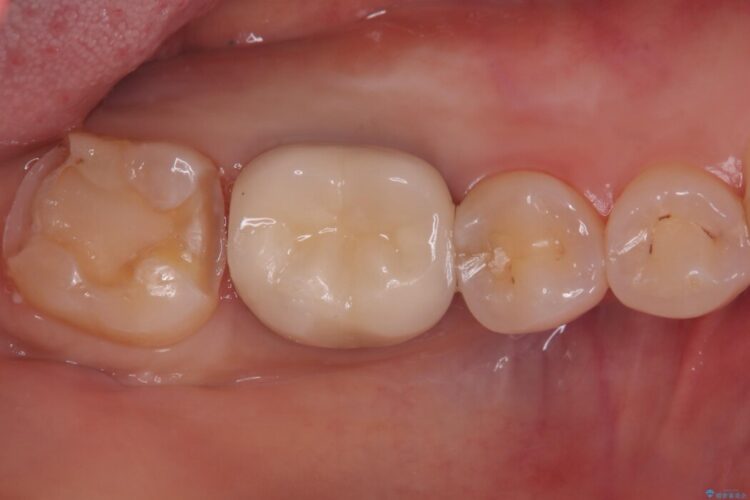

う蝕、古い材料を全て除去し、セラミックインレーでやり替えることとしました。

右下奥歯の広範囲な虫歯と劣化した古い詰め物をすべて除去し、新しくセラミックインレーで修復しました。装着時にはラバーダムを使用し、湿気を遮断した状態で精密に接着させています。